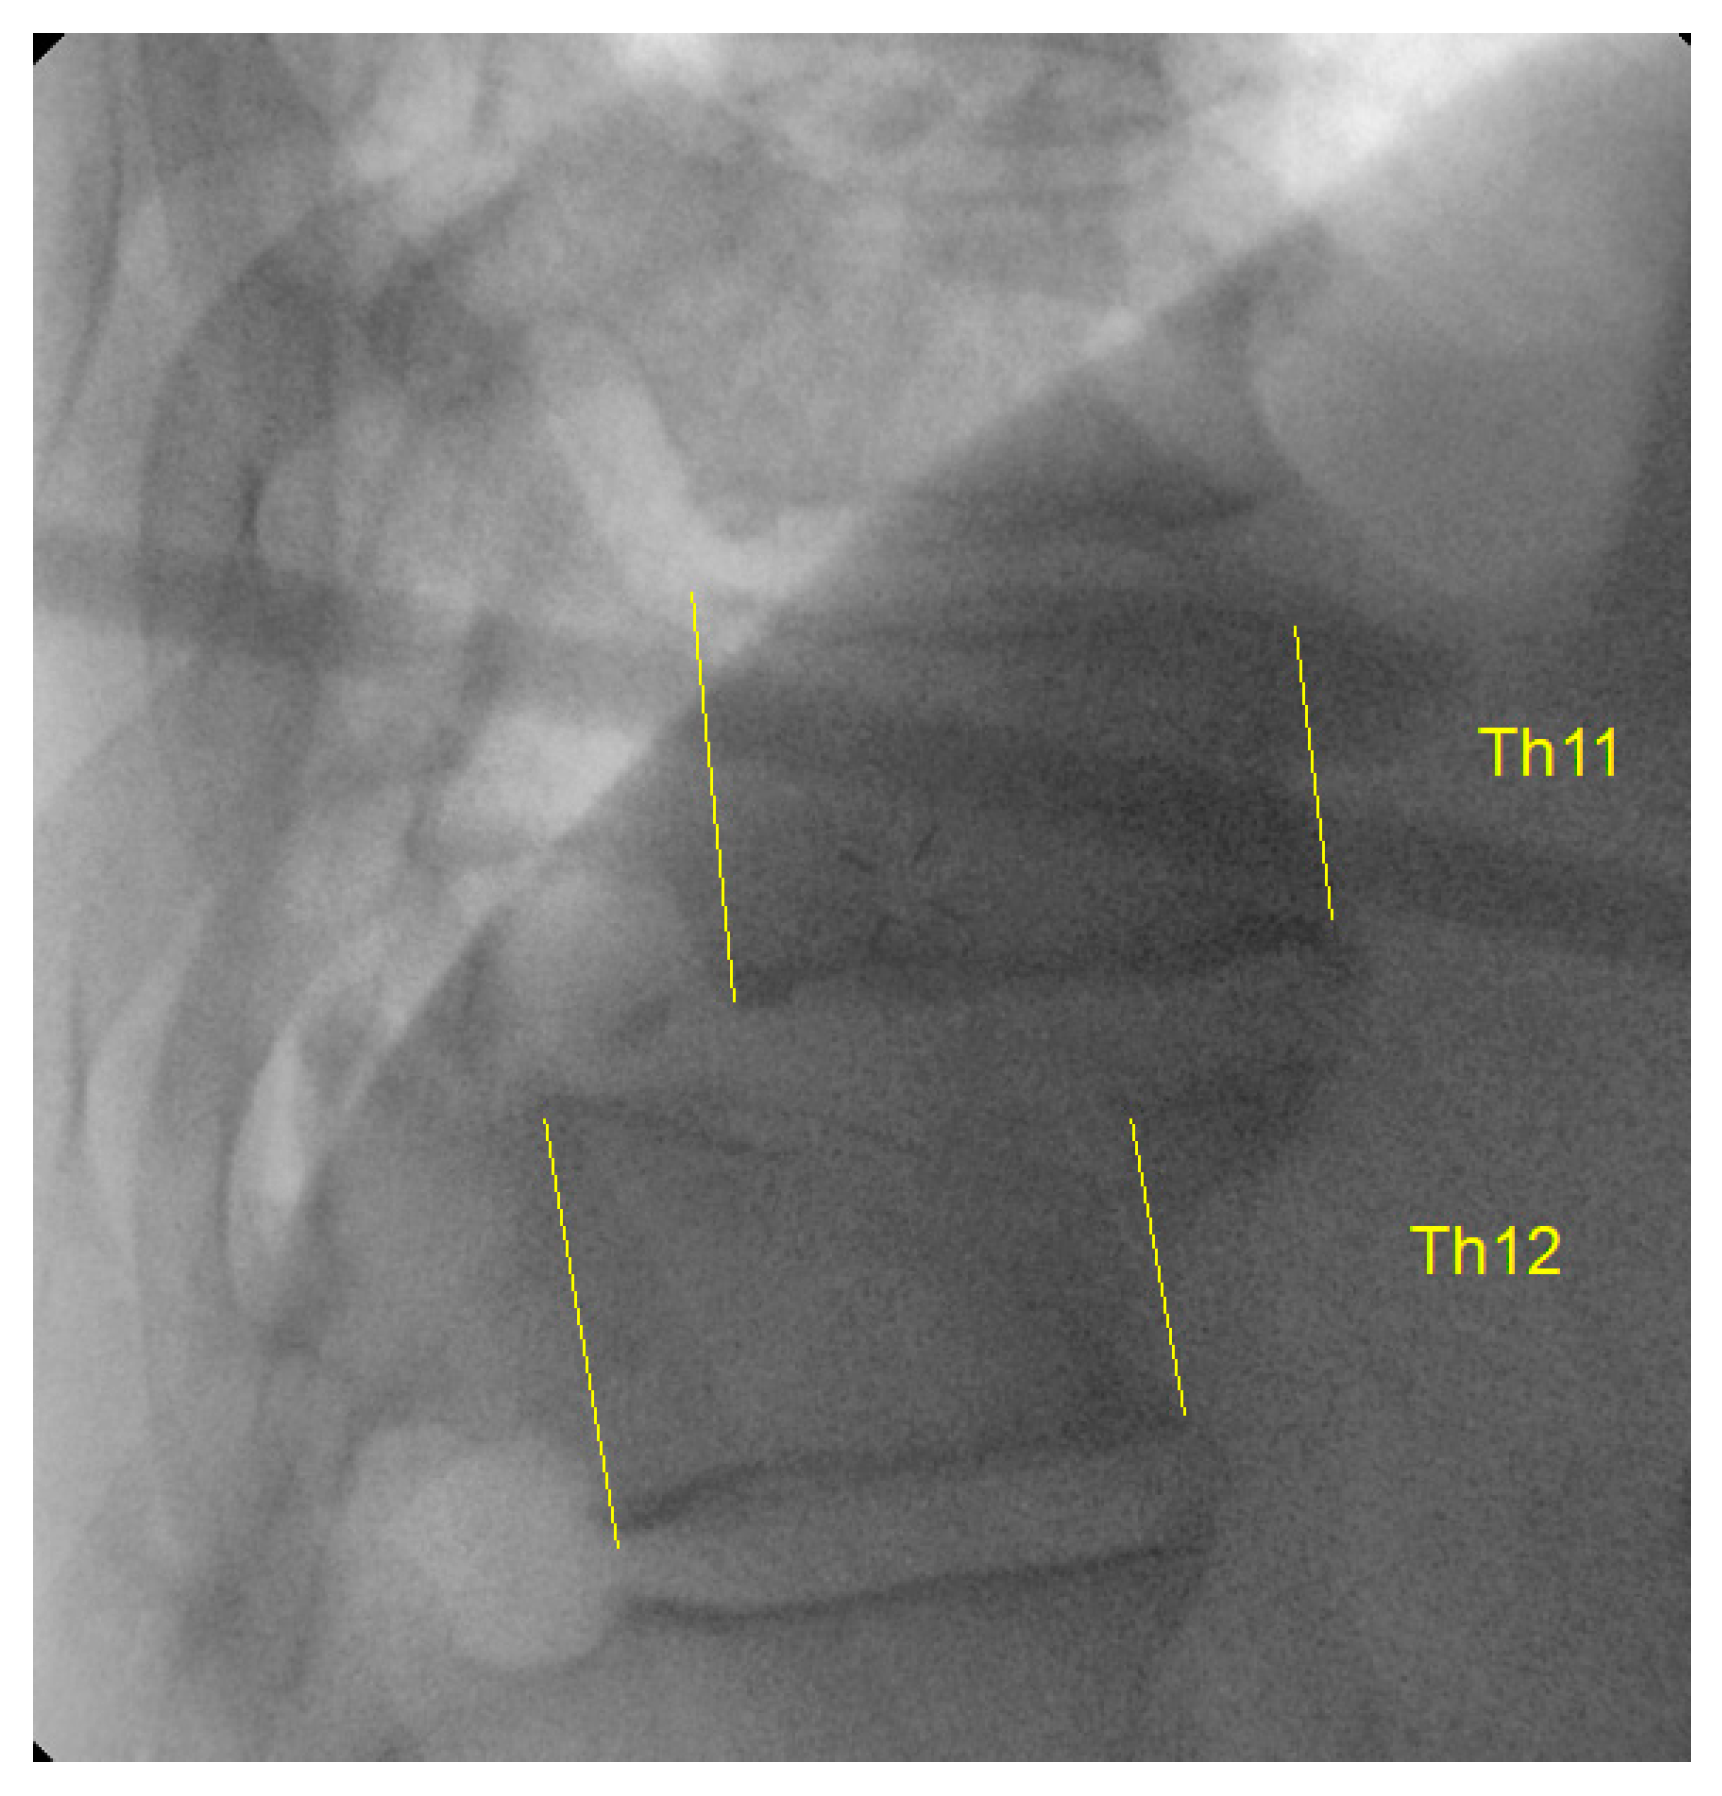

Figure 3. Intraoperative fluoroscopic image showing dislocated Th11-Th12 levels.